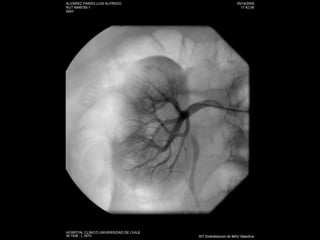

Angiografía

Estudio No invasivo: AngioTC Doppler Angio RM:  esclerosis sistémica  nefrogénica Invasivo: angiografía